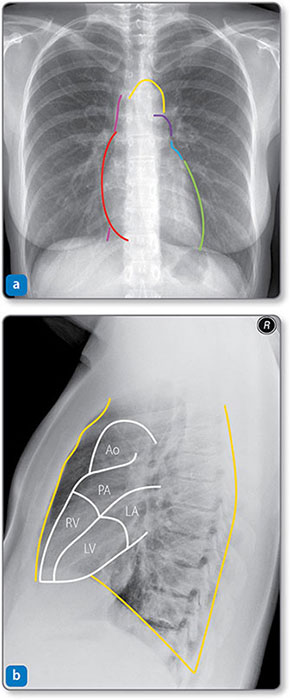

The heart is in the middle mediastinum with its apex pointing inferolaterally (Figures 1.3 and 1.4). It is posterior to the sternum, costal cartilages and left lung pleura and superior to the left diaphragm. Structures adjacent to the posterior heart 2are the thoracic vertebrae, esophagus and descending aorta (Table 1.1).

Figure 1.4: Radiographs showing the borders of the heart and great vessels. (a) Frontal view. The right heart border (red) is formed mainly by the right atrium. The left heart border is formed mainly by the left ventricle (LV, green) and the left atrium (LA, blue). The inferior surface (against the diaphragm) represents the right ventricle (RV). The vena cava (pink) is above and below the right heart border, and the aortic arch (yellow) and pulmonary trunk (purple) are above the left atrium. (b) Lateral view. The anterior, posterior and inferior relations of the heart (orange) are formed by the sternum or left lung pleura, thoracic spine and diaphragm, respectively. Ao, aorta; PA, pulmonary artery.